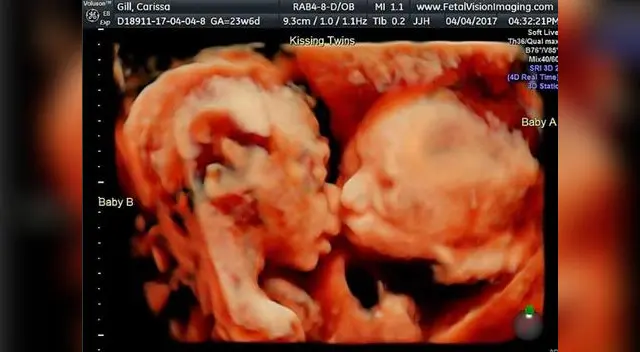

Instagram: ecografía de bebes besándose causa sensación en Internet [FOTOS Y VIDEO]

Una increíble imagen en la que dos gemelos se besan y abrazan en la barriga de su madre ha generados tiernas reacciones en Instagram. "Si yo fuera Beyoncé esta foto se hubiera hecho viral en segundos", dijo la emocionada madre que radica en Estados Unidos.

La tecnología lo puede todo y el amor de hermanos también. Clarisa Gil, una ciudadana norteamericana subió a su cuenta de Instagram una ecografía de sus hijas Isabella y Callie de 25 semanas de gestación en el que nítidamente se puede observar un tierno beso y abrazos de las hermanas.

Esta imagen dio la vuelta al mundo en segundos e incluso Clarissa Gil y su esposo fue invitada a un programa de espectáculos norteamericano (FOX 29) para dar a conocer su increíble historia. La revista The Sun también abordó su simpático caso. "Quiero compartir esta historia con el mundo".

La popular madre de las dos gemelas, (Isabella y Gil) es toda una moda en Instagram, pues también tiene fotografías y vídeos desde la primera semana de su embarazo hasta estos días días. "Ya quisiera que nazcan mis hijas y poder tenerlas conmigo, estoy muy emocionada del amor que se tienen ambos. Somos unos padres muy felices", dijo Clarisa.